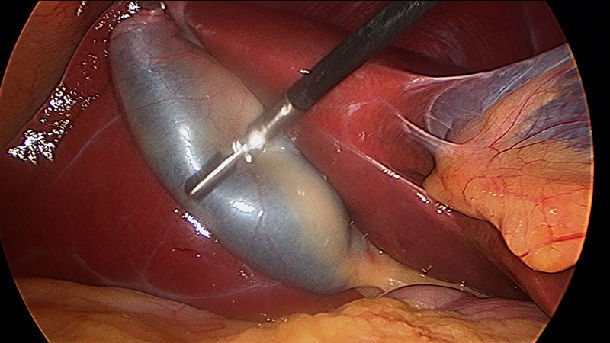

直径小于2cm的胆囊息肉,可行腹腔镜胆囊切除;超过2cm或高度怀疑恶变,应剖腹手术,以便于行根治切除。